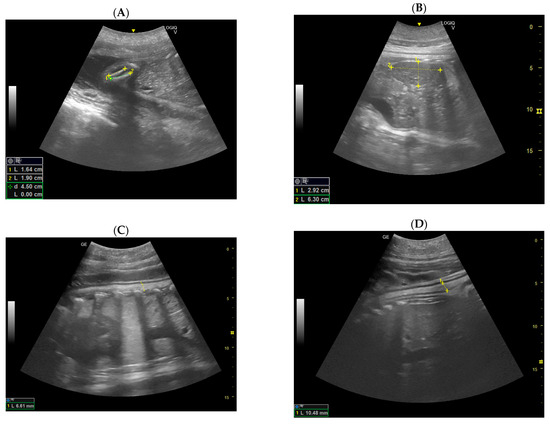

- Day 129 ± 3: Embryonic cardiac mechanics is displayed, as a point of maximum fluctuation of the echoes. It is possible to recognize from the beginning of the heart rate. The heart rate was measured once the cardiac mechanics became visible and remained constant between 205 and 155 bpm until the ninth month of pregnancy. For the next 3 months, it stabilized at 140–135 bpm (Figure 3).

- Day 162 ± 2 and 170 ± 2: Skeletal formations, such as the cranial bone, vertebrae, costal bones, limbs, and detailed regions such as fingers, were first observed. The first abdominal organs to be visualized are the stomach and the urinary bladder, which appear as distinct and anechoic cavities. At the same time, it was possible to observe fetal movements.

- Day 186 ± 2: It is possible to identify the heart, lungs in the thorax, diaphragm in the middle, and liver and stomach in the abdomen. (D) Lungs appear as hyperechoic structures on the sides of the heart, and the latter seems to have a similar echogenicity compared to the liver (Figure 4).